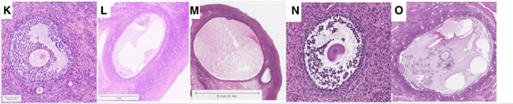

-Nang có hốc: có thể đo được bằng mô học hoặc siêu âm. Noãn bào được bao quanh bởi cụm tế bào cumulus trong một khoang chứa dịch (antrum), được bao bọc bởi nhiều lớp tế bào hạt thành (mural granulosa cells). Các lớp này được ngăn cách với lớp vỏ trong (theca interna) bởi màng đáy, và bên ngoài cùng là lớp vỏ ngoài (theca externa). Nang noãn người có khả năng tái khởi động quá trình giảm phân khi đạt đường kính từ 2–5 mm, với đường kính noãn bào vào khoảng 100–120 µm. Đường kính nang tối thiểu để có noãn trưởng thành có tiềm năng phát triển là khoảng 5–7 mm (hình K-O).

K |

Hốc sớm (Early antral) |

<2mm |

L |

Trước chọn lọc (Preselection antral) |

2-5mm |

M |

Chọn lọc (Selection antral) |

6-9mm |

N |

Trội (Dominance antral) |

10-15mm |

O |

Tiền phóng noãn (Preovulatory antral) |

16-28mm |